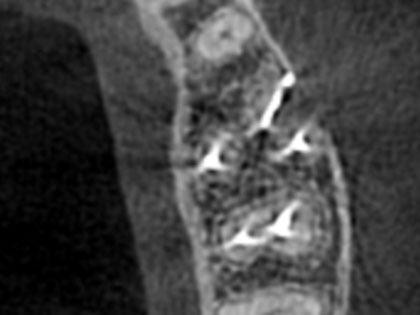

• 術後の写真がこちら

• 歯根端切除の術後6

• 歯根端切除の術後7

• 歯根端切除の術後8

• 歯根端切除の術後9

• 歯根端切除の術後10

• 歯根端切除の術後11

• 歯根端切除の術後12